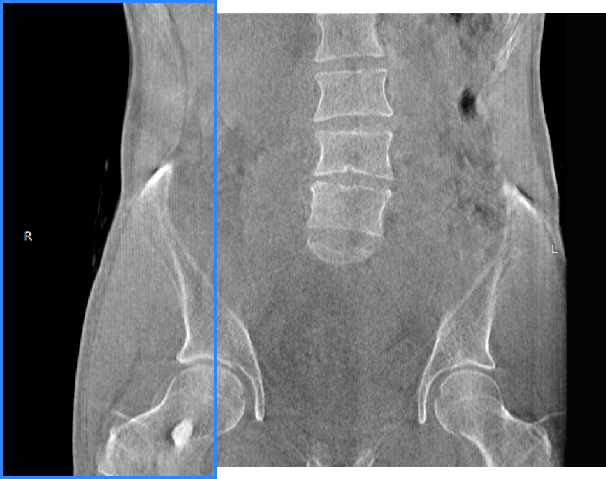

髋关节

腰椎